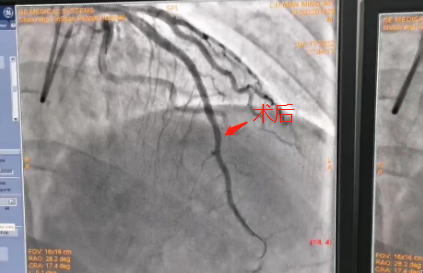

急诊科接诊医生介绍说,刘先生入院时血压197/128mmHg,肌钙蛋白明显升高,心电图提示:急性前壁心肌梗塞,需要立即手术治疗。病情危急,刻不容缓!医院立即启动急救绿色通道,将刘先生送介入中心导管室。完善术前准备,与家属沟通、签字后,急诊PCI手术开始了。造影显示,前降支中远段端严重狭窄。令人欣慰的是,手术进行得很顺利。半个小时后,刘先生就被推出了手术室。术后刘先生被安全送至心内科住院病房,胸痛症状明显缓解。